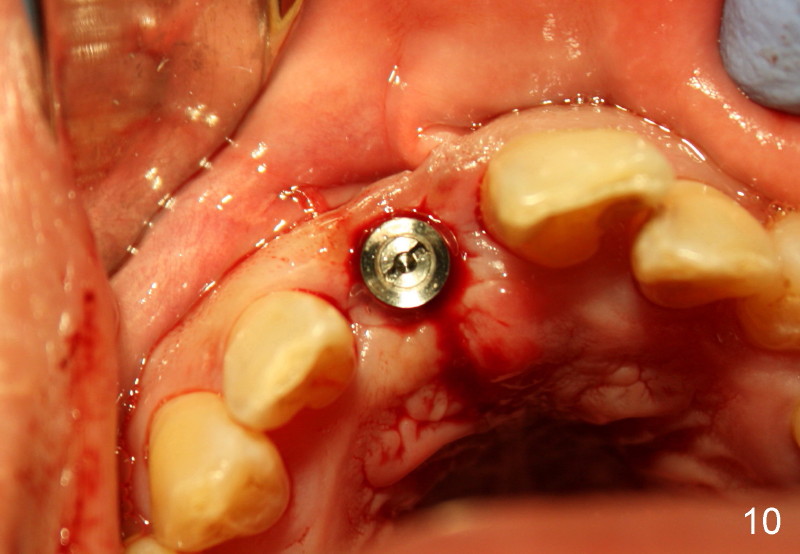

Two more weeks later, D2 implant (4.5x5.5x20 mm) is placed (Fig.9,10).  Fig.7 D2 thin socket former at ~ 16 mm depth, Fig.8 D2 medium socket former at ~ 19 mm.

Implant threads are at crest level (Fig.9).  Is there any potential problem?